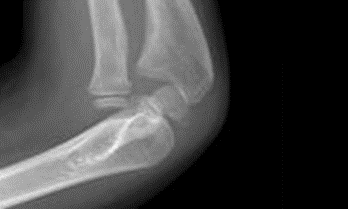

Monteggia fractures

This is a displaced ulna fracture, usually proximal, with a radial head dislocation. To identify a radial head dislocation, check that the capitellum and radial head are aligned on AP and lateral X-rays.